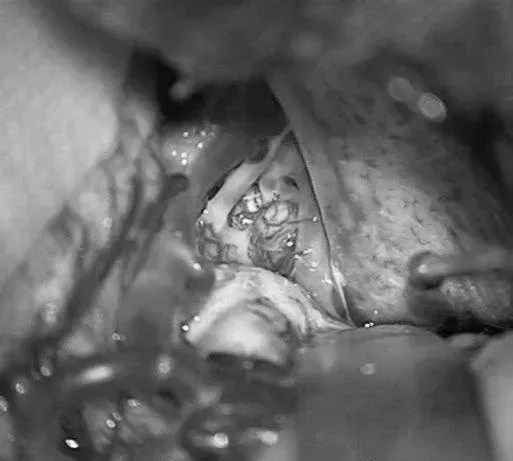

▼右侧眶颧开颅,经侧裂入路,牵开颞极暴露来自ICA鞍上段、MCA的M1段、PCA的P2段和小脑幕切迹。

▼电凝供应颞叶内侧面型AVM的PCA的P2供血支,减少畸形团血供。

- 第1步:使用眶颧入路垂直显示AVM,经侧裂分离,就像前往基底动脉分叉动脉瘤的入路。

- 第2步:移除眶骨可以比翼点入路提供更靠前的径路,使术野延伸到颞叶内侧表面。卸下颧弓以便颞叶向后外侧回缩,进一步拓宽术野。向后外侧回缩显露颞叶内侧面,使之成为一个凸面的入路。总的来说,眶颧开颅缩短了到达AVM的距离,并增加显露。分离侧裂将颞叶内侧面从粘连的额叶上分开,打开颈动脉池和脚间池,分离围绕钩回的AChA。

- 第3步:沿岛叶内侧和下方进一步分离至PCA。颞叶内侧面型AVM向深部引流至BVR。

- 第4步:牵开颞极,且不损伤重要的引流静脉。使用眶颧-经侧裂显露AVM基底部,可以看到来自AChA和PCA的P2段,以及来自PCoA(AntThaP)、TempPolA和ATA的供血支。